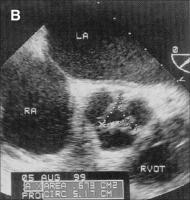

Zerebrovaskuläre Komplikationen nach retrograder Katheterisierung der Aortenklappe bei Patienten mit Aortenklappenstenose - Fact or Fiction?

Journal für Kardiologie - Austrian Journal of Cardiology 2004; 11 (12): 511-514 Volltext (PDF) Summary Abbildungen